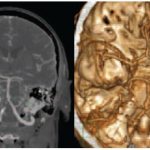

Treatment necessarily begins with diagnostics, which includes examination and x-rays. Once the cause of the patient’s pathological condition is identified, methods for eliminating it are determined.